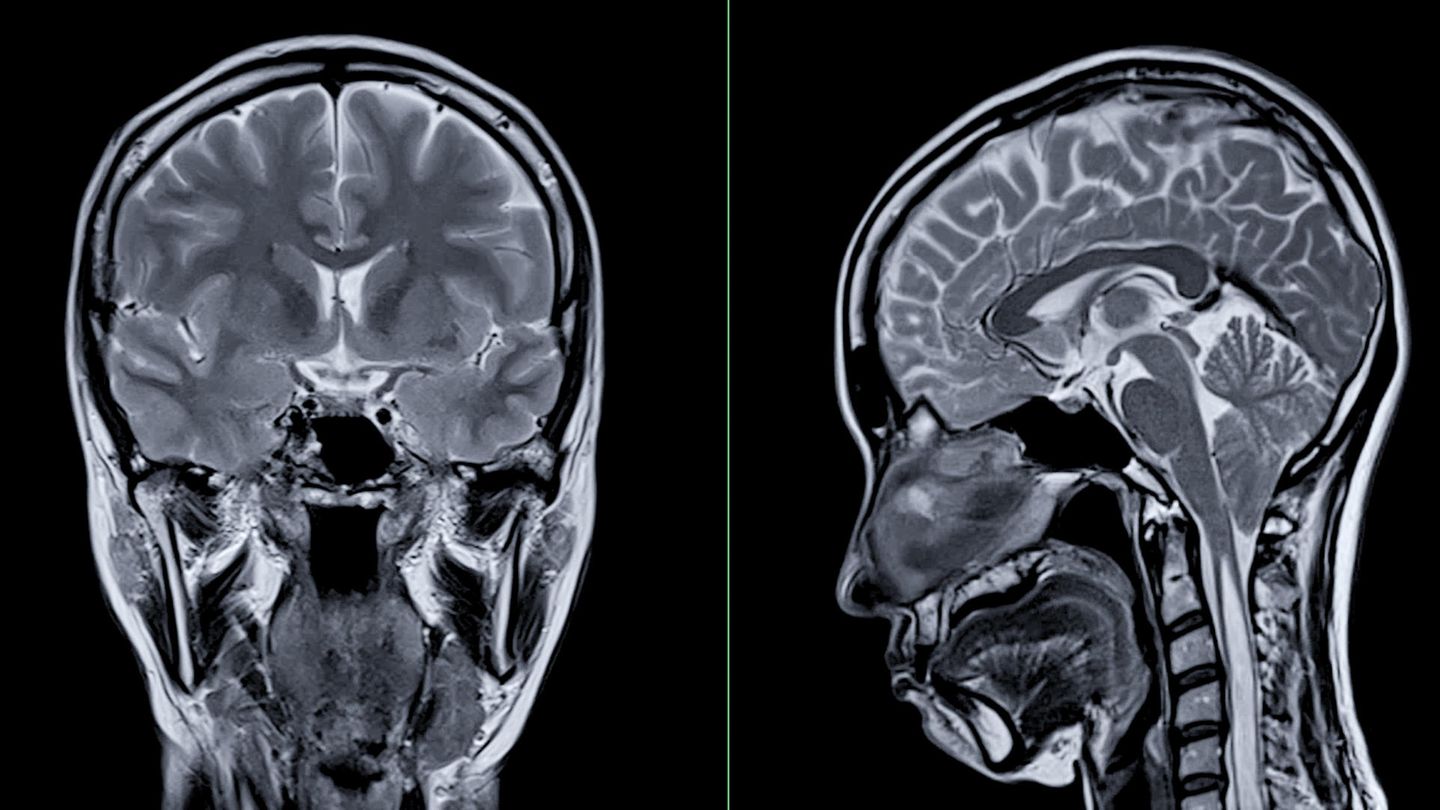

MRT-Aufnahmen von Kopf und Gehirn (Symbolbild): Eine Studie zeigt eine auffällige Gehirnentwicklung bei Kindern und Jugendlichen während der Corona-Zeit – eine mögliche Folge der Pandemie-Erfahrung

© mr.suphachai praserdumrongchai / Getty Images